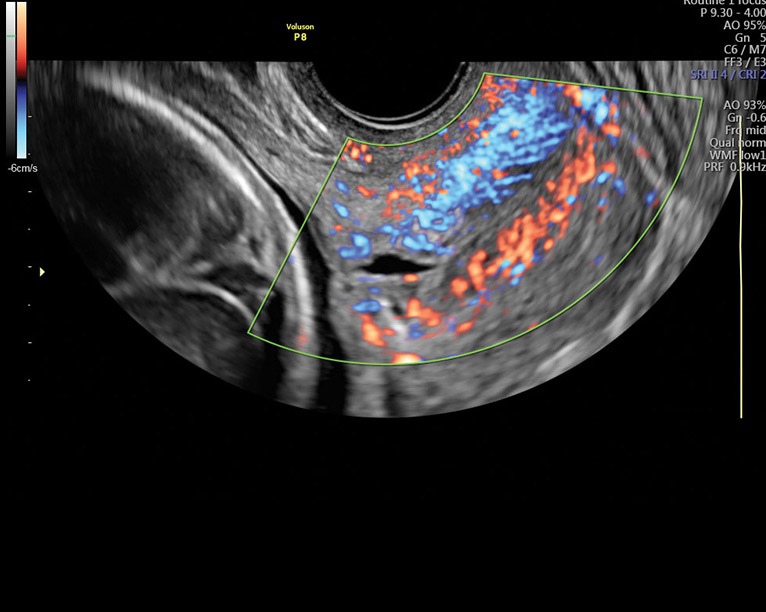

• Усовершенствованное цветовое доплеровское картирование: Эта функция позволяет получить более детальное изображение сердечно-сосудистой системы и ее функциональных систем. Она выводит обследование на новый уровень, обеспечивая более точную визуализацию и анализ данных.

Аппарат Voluson P8 сочетает простоту использования, высокую точность диагнозов и эффективность обследования в области акушерства и гинекологии. Он предоставляет медицинскому персоналу мощный инструмент для более точной диагностики и улучшения обслуживания пациентов.

• Работа в В-, М-режимах, наличие импульсно-волнового, цветного допплеровского картирования, тканевого, энергетического и высокочувствительного направленного энергетического допплера (HD-Flow), тканевая гармоника

• Высокочувствительный допплер (HD-Flow), многолучевое сложносоставное сканирование (CRI), Speckle Reduction Imaging (SRI), SonoBiometry (автоматическое измерение BPD, AC, HC, HL, FL)